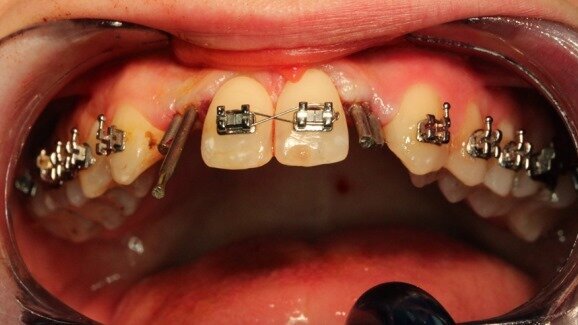

Do gabinetu zgłosiła się 23-letnia pacjentka z hipodoncją siekaczy bocznych szczęki po zakończonym leczeniu ortodontycznym aparatem stałym, skierowana do dalszego leczenia implantoprotetycznego. Badaniem klinicznym stwierdzono wystarczającą przestrzeń na koronę protetyczną, a widoczna na pantomogramie odległość między korzeniami sąsiednich zębów sugerowała możliwość bezpiecznego zastosowania wszczepów o śr. ok. 4-5 mm.

Badanie grubości tkanki kostnej wyrostka zębodołowego w znieczuleniu miejscowym i poprzeczne skany DTS dały obraz odmienny (Ryc. 6). Wobec wymiaru poprzecznego kości 2,6 mm zastosowano wszczepy igłowe o śr. 1,5 mm. Wprowadzono je bez otwierania płata, w znieczuleniu nasiękowym na szczycie wyrostka niewielką ilością 4% artykainy, zgodnie z przytoczoną metodologią (Ryc. 7). Ustabilizowane wszczepy połączono naddziąsłowo prętami tytanowymi o takiej samej średnicy za pomocą zgrzewarki wewnątrzustnej Mondaniego. Wolne przestrzenie uzupełniono kompozytem, powstałe pełne struktury oszlifowano, nadając im kształt filarów protetycznych (Ryc. 8) i pobrano wyciski do ostatecznych koron porcelanowych. Zabieg zakończono zacementowaniem przygotowanych w gabinecie prowizorycznych koron kompozytowych (Ryc. 9 i 10).